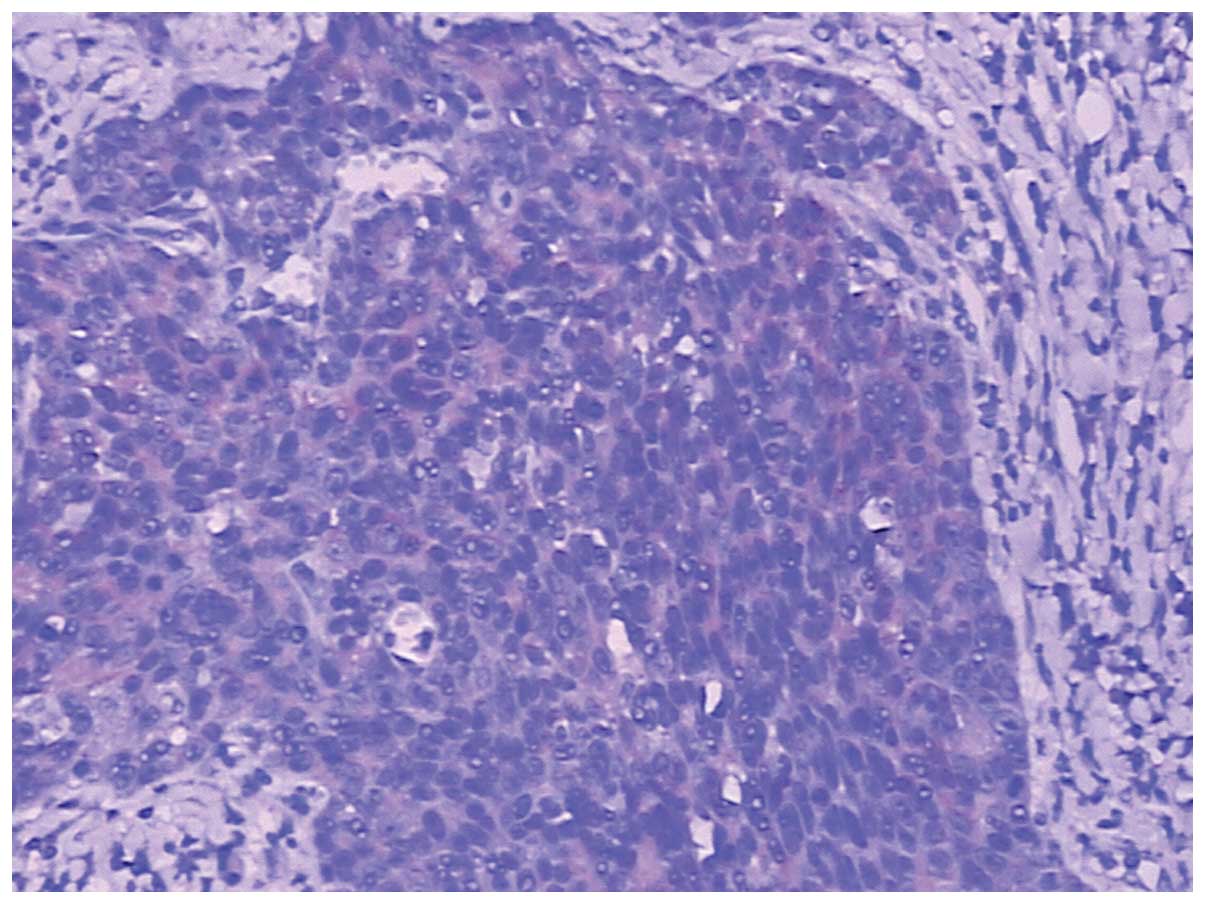

Histopathology revealed that the SCC infiltrated into the serosal fibrous tissue, lamina muscularis and submucosa of the gastric wall (Fig. 3A–C); however, there was no cancer cell infiltration into the mucosa. The surgical margins were negative, however, metastasis to one lymph node in the lesser curvature of the stomach was observed. Furthermore, the esophagogastric junction was negative for the tumor. The immunohistochemical staining was positive for cytokeratin (CK)5/6, p63, CKpan and glutathione S-transferase π (Figs. 4–7), and negative for cluster of differentiation (CD)56, CDX-2, chromogranin A, CK20, CK7, S100, Syn, Villin, P-glycoprotein, epidermal growth factor receptor, topoisomerase II and p53. The Ki-67 proliferation index was ~50% (Fig. 8). Due to the progression of the disease, postoperative chemotherapy was recommended, and the patient and the patient’s family consented to four sessions of chemotherapy. At the end of the 12-month follow-up, which was conducted using ultrasonography and CT, the patient had survived and there was no evidence of recurrence and metastasis.

Figure 3

Tumor cells were observed in the (A) gastric serosa fibrous tissue, (B) lamina muscularis and (C) submucosa. (Hematoxylin and eosin staining; magnification, ×100).